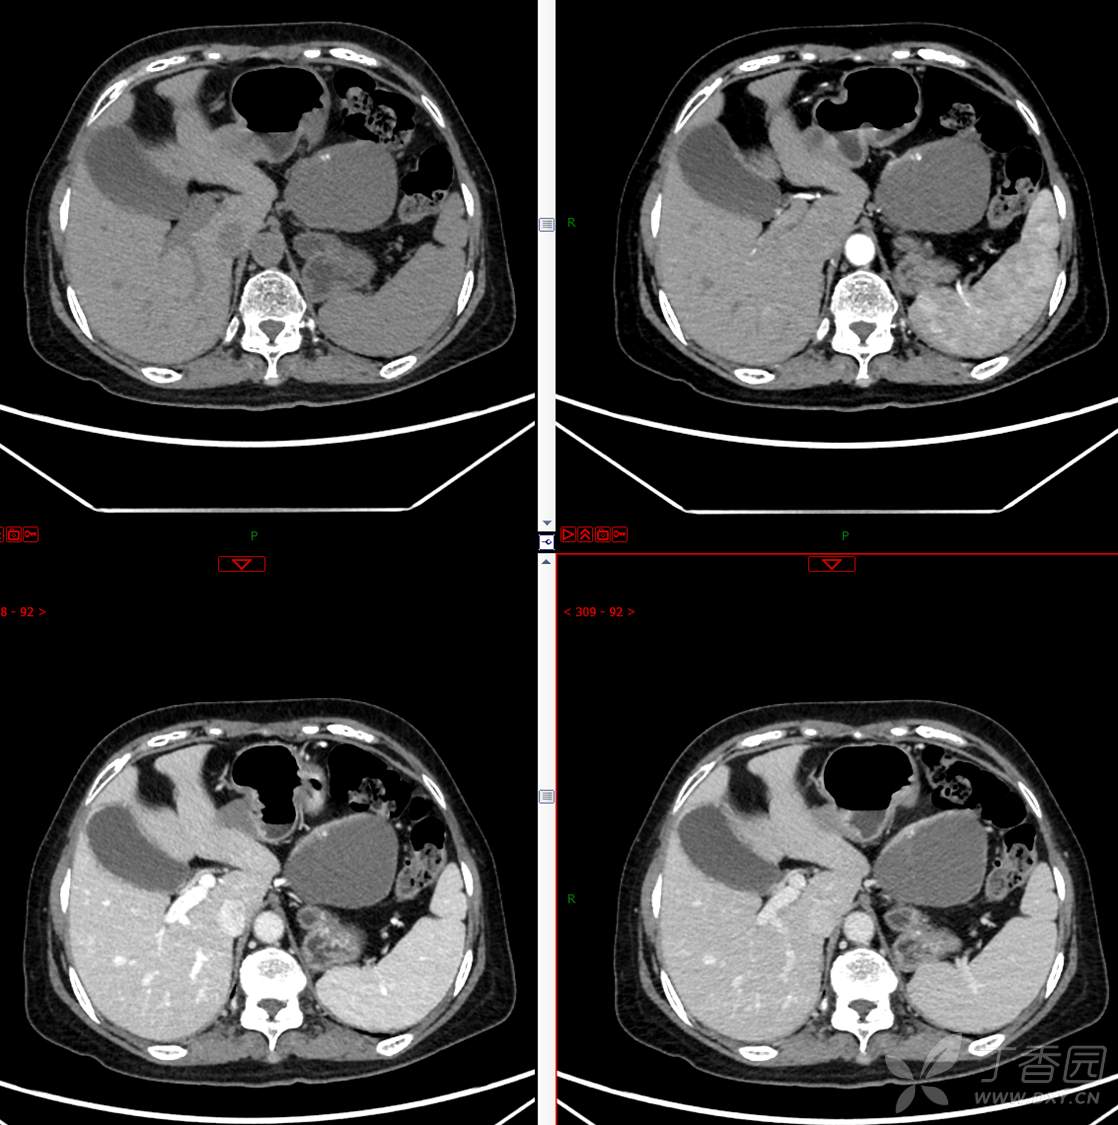

主 诉:发现胰腺占位性病变3月

现病史:患者3月前就诊于**市人民医院行腹部增强CT发现胰尾占位性病变,无腹痛、腹胀,无恶心呕吐,无黄疸,无呕血黑便,无胸闷憋气,无寒战高热,未行特殊治疗